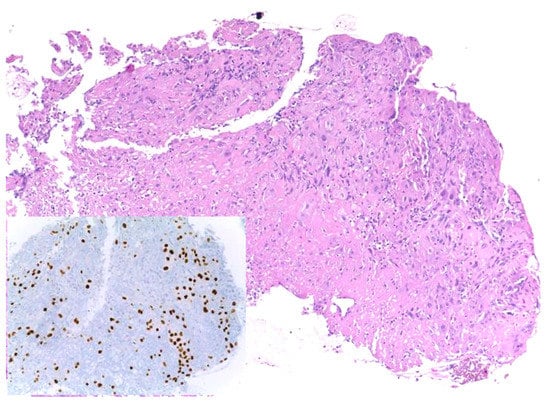

Similar changes can be observed in recurrent/persistent postradiation laryngeal SCCs. Figure 1 illustrates a postradiation recurrent SCC of the vocal cord. The tumor shows no connection with the surface epithelium and consists of cords and a small island of tumor cells within a fibrotic stroma. Although the significance of these findings for the biology of the tumor remains to be fully determined, they nevertheless have an impact on the evaluation of resection margins (Figure 2), as well as on the interpretation of histopathologic findings in biopsies, where neoplastic cells may be difficult to identify in small superficial samples, or if they are set within necrosis or fibrosis (Figure 3). In comparison, postsurgical recurrences of laryngeal SCC consist of irregular infiltrative tumor islands, but necrosis, acellular fibrosis with collagenization, inflammation, and the characteristic damage to vessels are usually absent (Figure 4).

Figure 3. Recurrent squamous cell carcinoma of the vocal cord following radiotherapy. In this biopsy specimen, tumor cells are obscured by necrosis and fibrosis. They are highlighted by the nuclear immunohistochemical staining for P40 (inset).